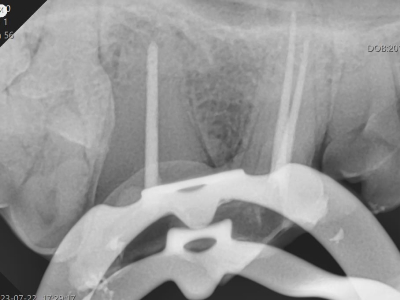

治療中のX線写真

治療中は何度もX線撮影し、歯内の状況を確認しながら治療を進めます。